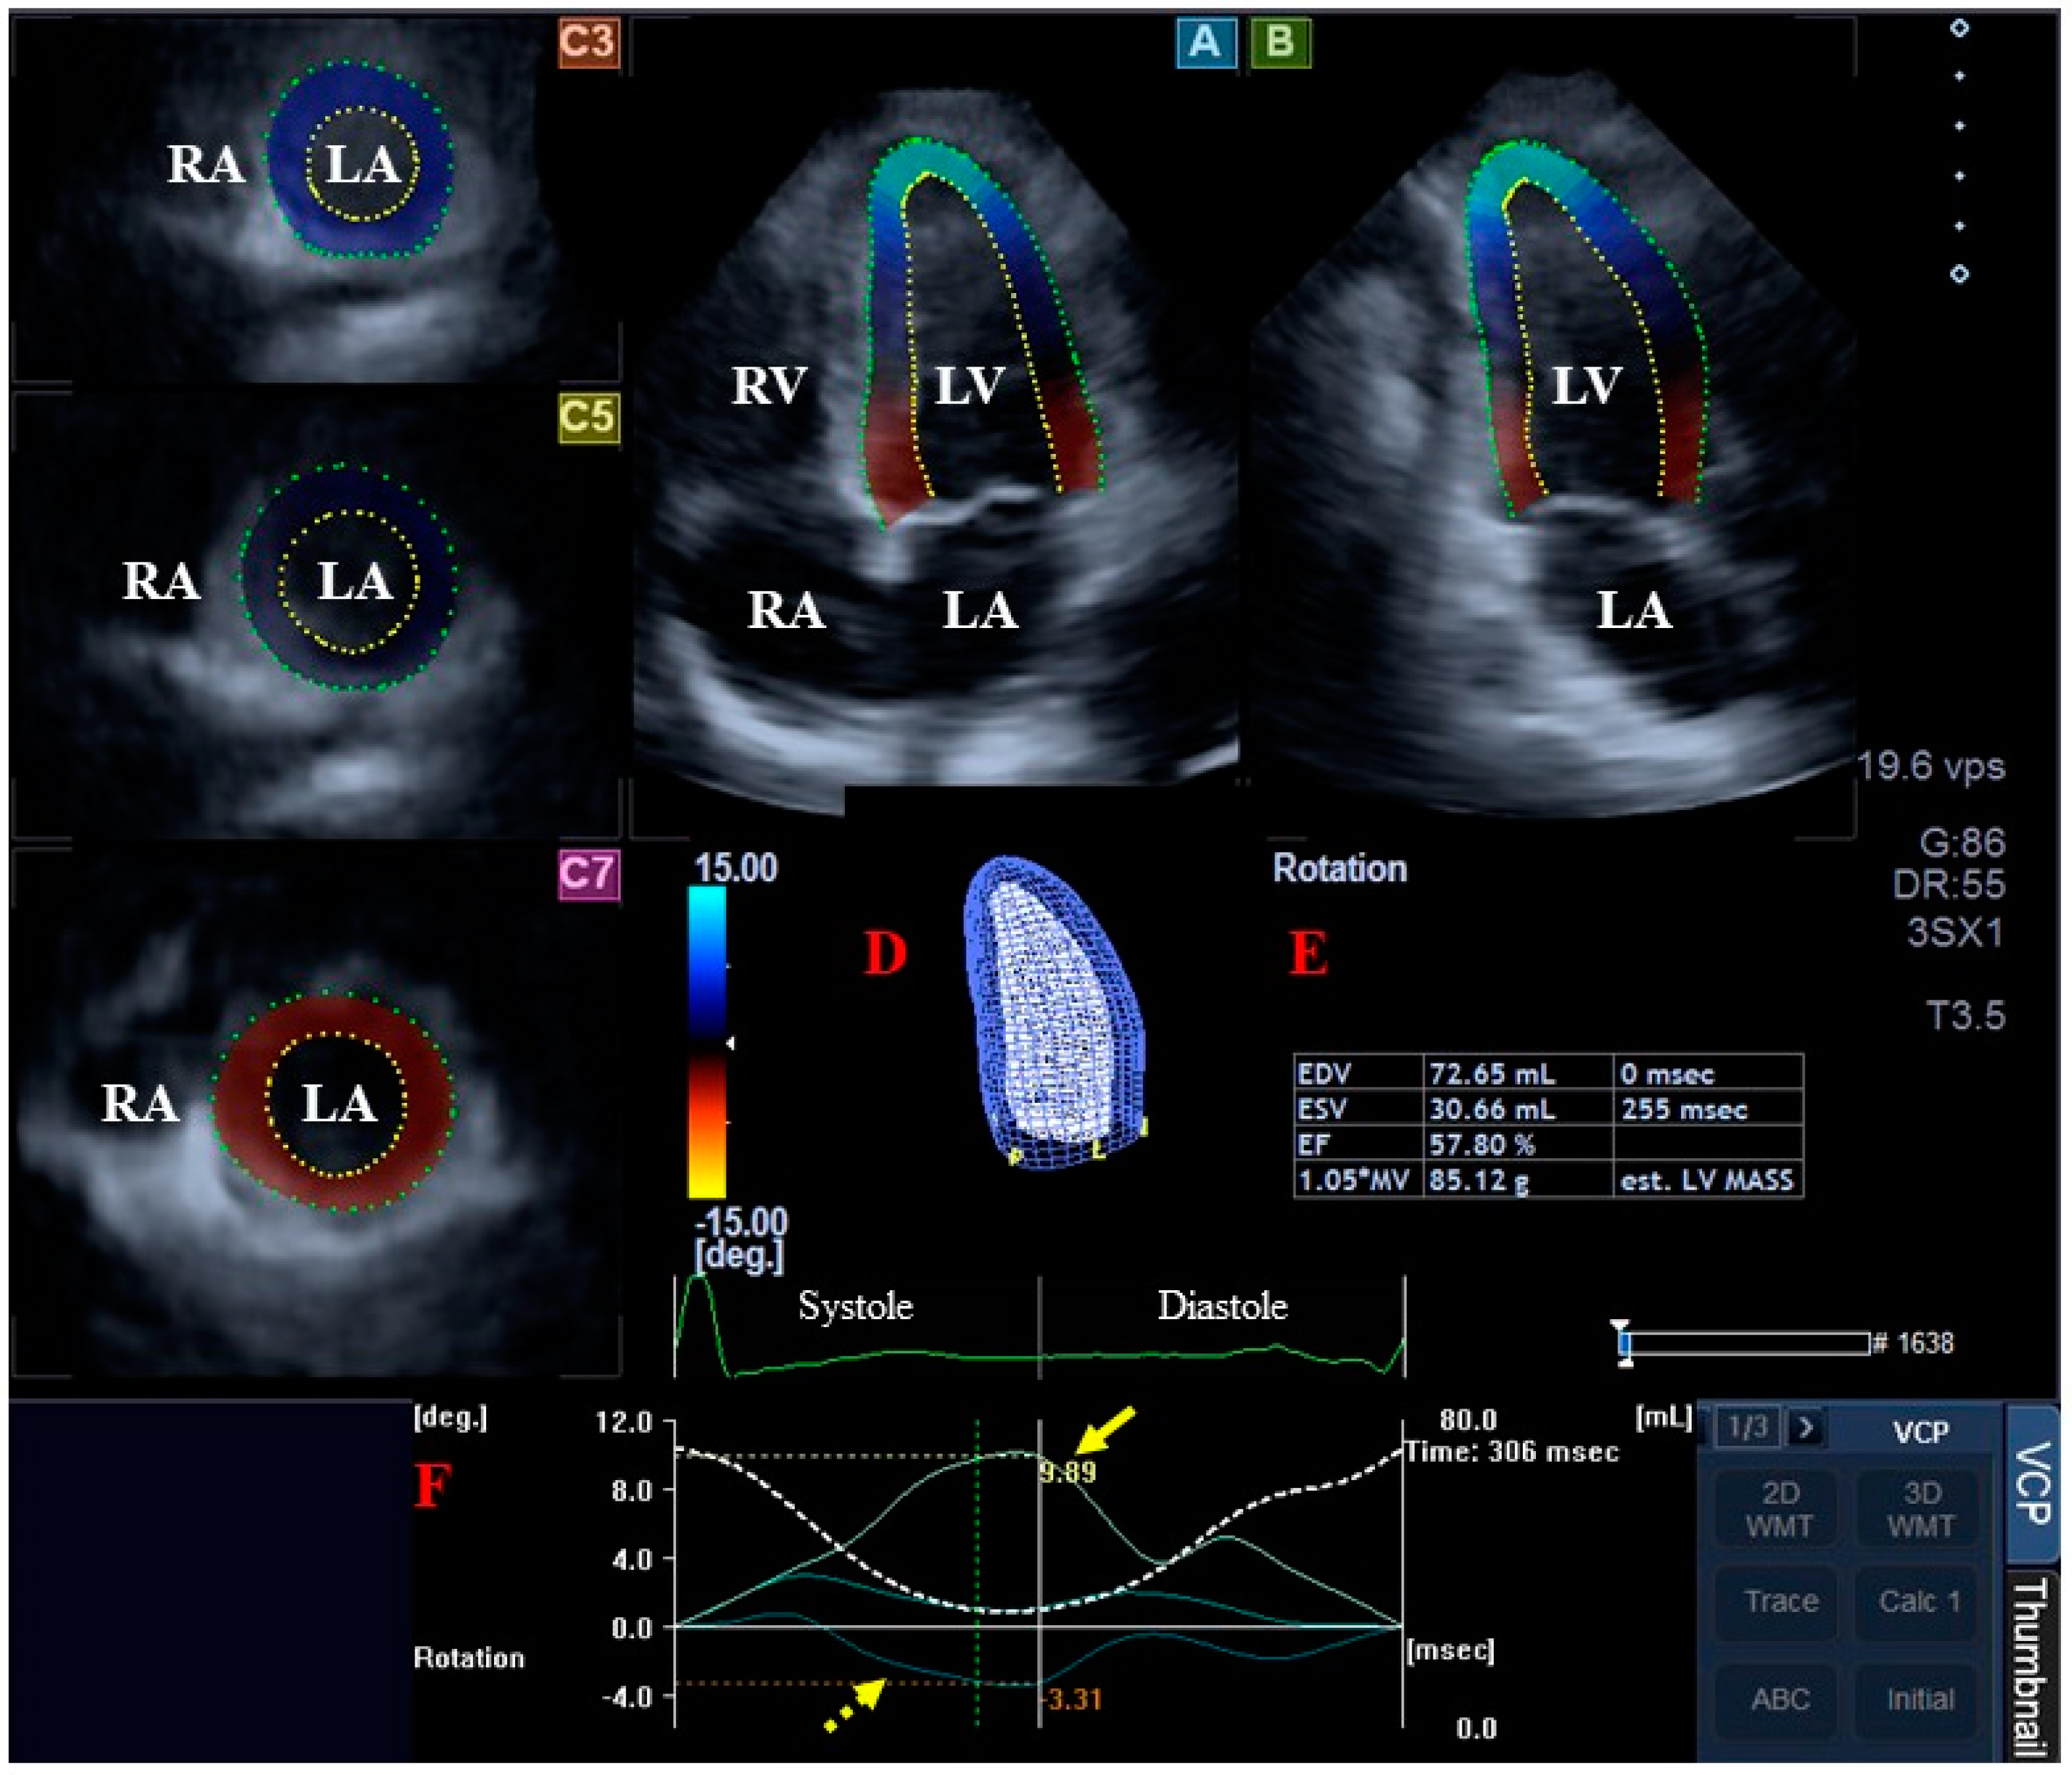

2.4. Determination of LV Rotational Mechanics

- clockwise basal LV rotation (in degrees);

- counterclockwise apical LV rotation (in degrees);

- LV twist (net difference in LV apical and basal rotations in degrees);

- time-to-peak LV twist (in milliseconds).